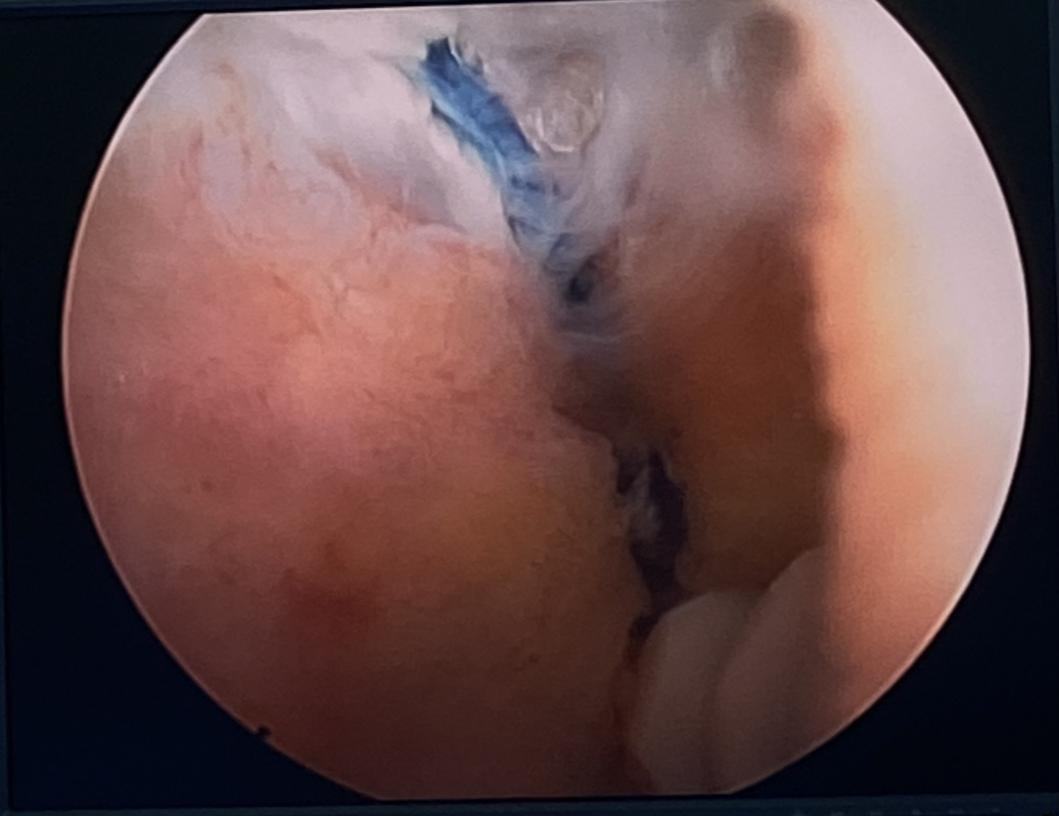

术中,医生在关节镜下探查可见肱骨头明显上移,冈上肌、冈下肌全层撕裂并严重回缩,残余肌腱纤薄并有脂肪浸润,肱二头肌长头腱炎性改变且部分磨损。在关节镜下,医生用2枚锚钉将肱二头肌腱长头转位固定。在对侧的下肢截取桥接移植物——半腱肌肌腱,镜下将移植物引入关节腔并以2枚锚钉牢固固定于大结节,至此手术已接近尾声,总共用时仅60分钟。此后于肩胛冈内侧解剖游离斜方肌下束,并通过相关器械将移植物的另一端传递到内侧切口与斜方肌下束以Krackow法编织缝合固定。术后探查移植物固定可靠,盂肱关节恢复正常对合关系。

关节镜下可见肱二头肌长头腱炎性改变且部分磨损,巨大肩袖撕裂。